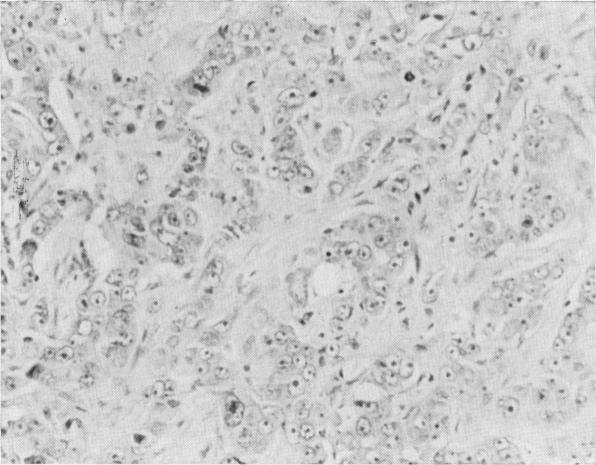

Records of 3085 patients registered with breast cancer at the Mersey Regional Cancer Registry have been analysed to evaluate the relative importance of possible prognostic factors. In a subgroup of 1759 patients, clinical stage and histological grade are shown to be strongly related to survival after treatment. In addition histological grade is related to the distribution of times to death after treatment. The results of this and 3 other studies have implications for the design and analysis of clinical trials in the primary treatment of breast cancer.

对默西地区癌症登记处登记的3085例乳腺癌患者的记录进行了分析,以评估可能的预后因素的相对重要性。在1759例患者的亚组中,临床分期和组织学分级与治疗后的生存率密切相关。此外,组织学分级与治疗后死亡时间的分布有关。本研究及其他3项研究的结果对乳腺癌初级治疗临床试验的设计和分析具有启示意义。